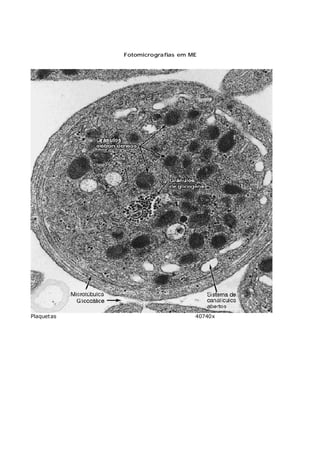

Fotomicrografias em ME

Plaquetas 40740x

Linfócito M = mitocôndria Nu= nucléolo N= núcleo 22000x

Neutrófilo 27000x

Eosinófilo M= mitocôndria N= núcleo EG= grânulo eosinófilo